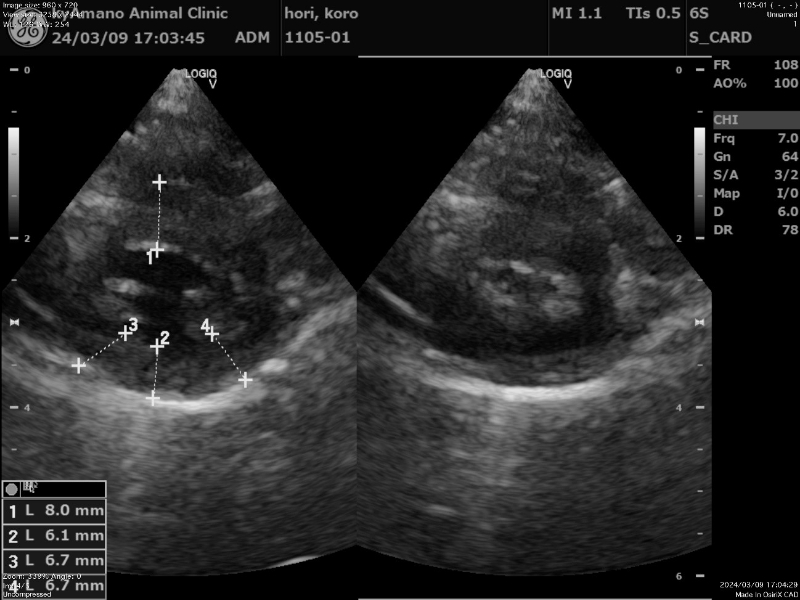

肥大型心筋症

猫ちゃんの心臓の疾患の中で最も多く発症する疾患です。

心臓の筋肉が分厚くなってきてしまうことで、血液が入る心臓の内腔が狭くなってしまい、血液を十分に送り出せなくなってきてしまいます。

高齢の猫ちゃんだけではなく、時には3カ月齢などの若い猫ちゃんでも認められます。健康状態の良好な猫ちゃんの中で15%が肥大型心筋症だったという報告もあります。ワクチンの時などに定期健康診断で心臓エコーを行うことで発見することができます。

血栓塞栓症で亡くなることが多いので、高リスクの動物には治療の提案をさせてもらうことがあります。 -